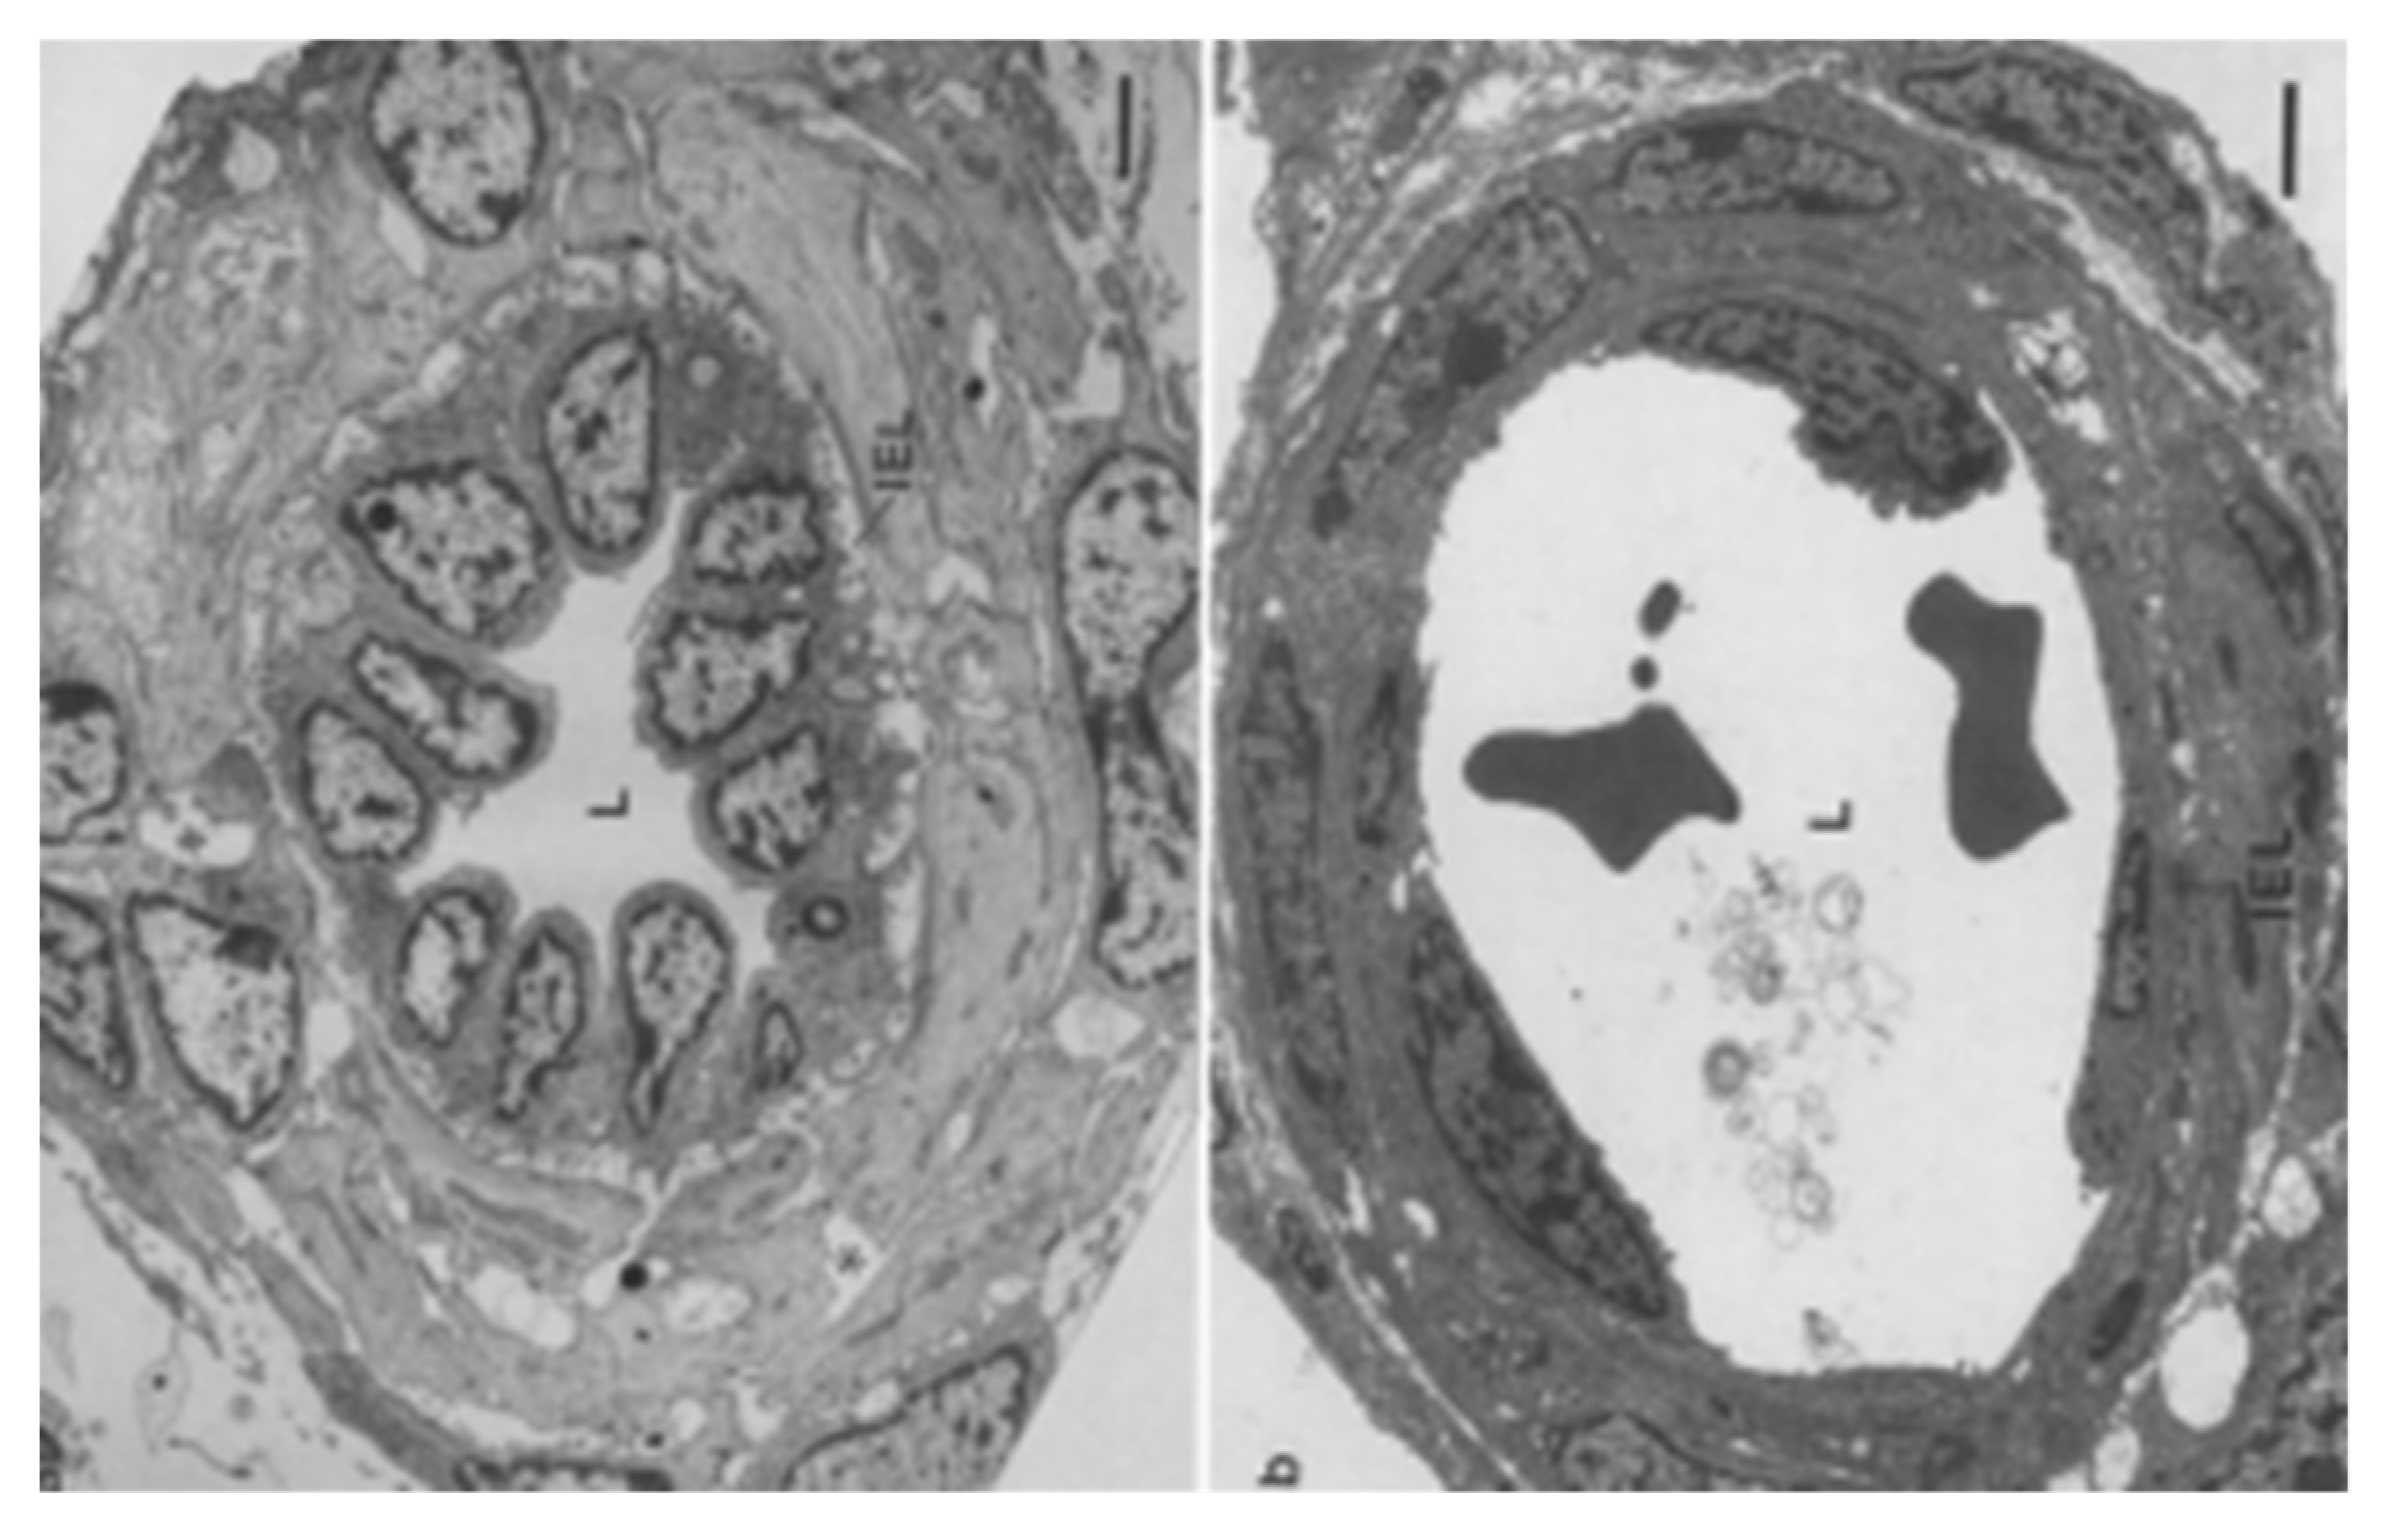

- Haworth, S.G.; Hall, S.M.; Chew, M.; Allen, K. Thinning of fetal pulmonary arterial wall and postnatal remodeling: Ultrastructural studies on the respiratory unit arteries of the pig. Virchows Arch A 1987, 411, 161–171. [Google Scholar] [CrossRef] [PubMed]

- Hall, S.M.; Haworth, S.G. Normal adaptation of pulmonary arterial intima to extrauterine life in the pig: Ultrastructural studies. J. Pathol. 1986, 149, 55–66. [Google Scholar] [CrossRef]